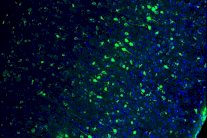

ويستخدم العلماء أداة تعديل الجينات الوراثية "كريسبر-كيس 9" لتنقية مليارات الحروف للشفرة الوراثية وتحديد هدفها الوراثي واختراق الحمض النووي بكفاءة.

واستعان العلماء بنحو 41 جنينا تبرع بها أزواج ليسوا بحاجة إليها للإخصاب الصناعي. وخلال السبعة أيام الأولى ينمو الجنين الطبيعي من خلية واحدة إلى نحو 200 خلية. كما يمر بالخطوات الأولى لتنظيم نفسه وتحديد وظائف خاصة للخلايا المختلفة.

ويكوّن الجنين جسما كرويا يطلق عليه اسم "الكيسة الأريمية" تحتوي على بعض الخلايا الخاصة لتكوين المشيمة والحويصلة السُرّية وأشياء أخرى.